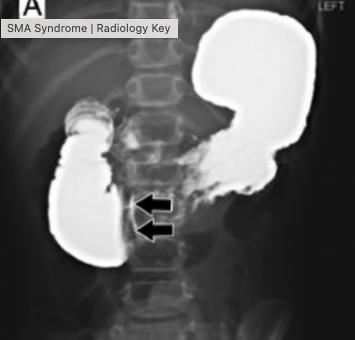

• 정의: 십이지장 3rd portion이 대동맥과 SMA 사이에 눌려서 발생

• 진단

• 상부 위장관 조영검사

• 영상 소견